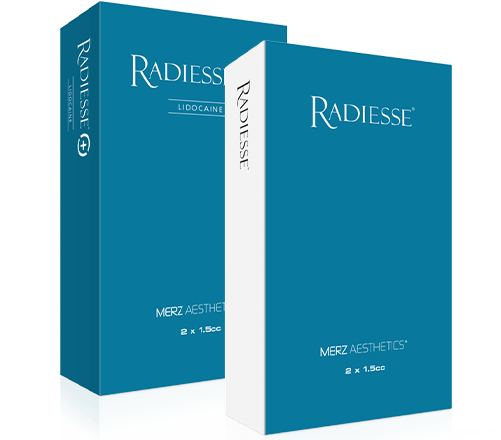

레디어스는 칼슘 미네랄 성분의 생체 친화적인 필러로 성분 특성상 점성과 탄성이 높아 시술 부위가 퍼짐 없이 유지되며,

촉감과 모양이 자연스러워 얼굴의 윤곽을 잡아주는 데 효과적입니다.

레디어스는 시술 직후 부터 미세한 칼슘입자가 분해되며

시술 부위 및 주변의 콜라겐 재생 촉진과 동시에 피부탄력 개선을 도와줍니다.